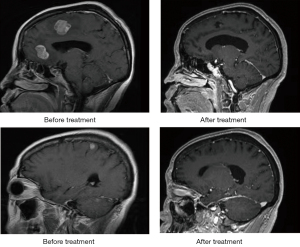

The identification of metastasis was confirmed by histopathological results and diagnosis of an intracranial metastatic tumor by double-dose enhanced magnetic resonance imaging (MRI) or enhanced computed tomography (CT) scan of the head, and by correlating these images with clinical symptoms and signs or after intracranial operation brain metastases were pathologically confirmed to be derived from the pulmonary adenocarcinoma.